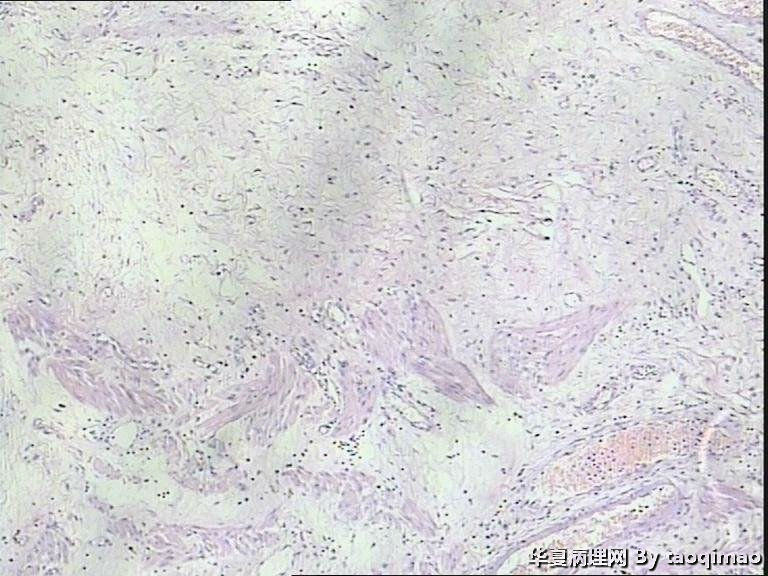

• 胃溃疡?图1

补取的组织

79岁女,胃溃疡,切除胃大部分,与脾有粘连,胃小弯侧可见一溃疡3x2.5x2cm,并且局部胃粘膜增厚,呈皮革胃样外观,切面灰白似粘液样。

巨大溃疡临床诊断,可是看了间质很浆糊,希望老师们给指点些

胃溃疡,黏液变,没看到明确的上皮样细胞